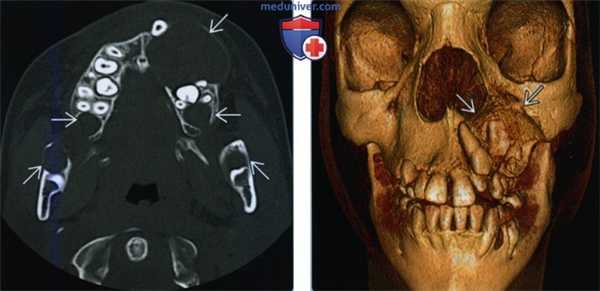

(Слева) При аксиальной КТ в костном окне у девятилетнего мальчика с синдромом базальноклеточного невуса визуализируются множественные двухсторонние литические очаги в верхней и нижней челюсти, типичные для кератокистозных одонтогенных опухолей.

(Справа) На 3D-реконарукции (вид спереди) у этого же ребенка лучше определяется объемное воздействие наибольшей опухоли на ближайшие зубы.